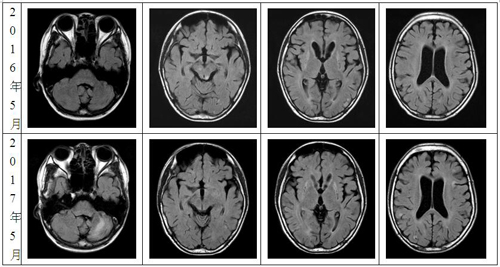

入院后辅助检查:头颅MRI (见图1): 患儿2016年5月与2017年5月头颅MRI T2 flair对比: 2017年5月左侧小脑半球新发病灶、双侧脑干异常信号消失、双侧基底节区异常信号不变、双侧颞顶枕叶皮层区多发异常信号增多或消失。视频脑电图(见图2):间歇期:双侧大脑半球广泛性癫痫样放电。发作期临床表现:先兆→眼睑阵挛→双侧非对称性强直(右颈肌著)→强直-阵挛(头面部著)→GTCS;发作期脑电图无侧向性。脑脊液常规未见异常。脑脊液乳酸:3.02mmol/L(正常值1.33-1.78mmol/L);血清静息乳酸3.22 mmol/L (1.33-1.78 mmol/L)。乳酸运动15分钟后:2.45 mmol/L,乳酸休息15分钟后:2.03 mmol/L;血清铜蓝蛋白、甲功三项、尿铜、血及脑脊液自身免疫性抗体检查均阴性。左侧腓肠肌骨骼肌肌肉活检 (见图3):骨骼肌肉组织可见肌间质轻度增生、散在分布的多角形萎缩肌纤维,未见线粒体脑肌病典型病理改变。骨骼肌电镜检查 (见图4):未见明显异常的线粒体。线粒体脑肌病基因检测结果提示 (见图5):血液中ND3 m.10197G>C, 54.4%, m.10197delG, 5.5%。骨骼肌肉样本中ND3 m.10197G>C与m.10197delG,突变负荷分别为82.1%和8.7%。

图1患儿2017年5月(第2行)与2016年5月(第1行)头颅MRI T2 flair对比:左侧小脑半球新发病灶、双侧脑干异常信号消失、双侧基底节区异常信号不变、双侧颞顶枕叶皮层区多发异常信号增多或消失。